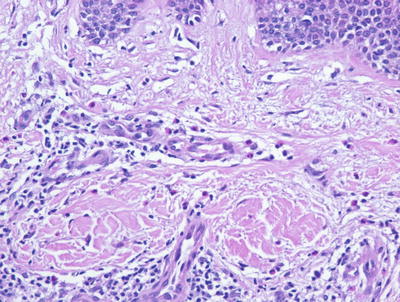

Allergic contact dermatitis is a spongiotic process, characterized by parakeratosis (except in the acute state), marked intraepidermal edema and abundant Langerhans cell microabscesses [45] (Fig. 1.13). In florid cases, the spongiosis results in microvesiculation. Eosinophils are abundant within the dermis and may extend into the epidermis (Fig. 1.14). A brisk lymphohistiocytic inflammatory infiltrate is present surrounding vessels of the superficial vascular plexus. Ordinarily, the inflammation does not extend into the lower portions of the dermis [46, 47].

Fig. 1.14

Allergic contact dermatitis frequently displays spongiotic microvesicles that contain eosinophils. Abundant eosinophils are characteristic of this disease